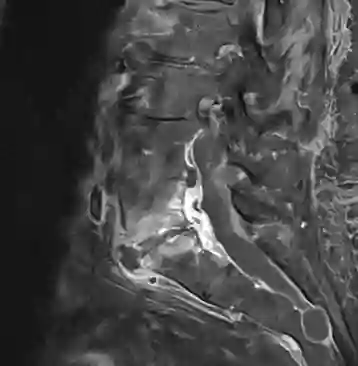

Spondylodiscitis MRT

Sagittales MRT einer T1 Kontrastmittelsequenz eines Patienten mit einer Spondylodiscitis im Segment LWK5/SWK1.